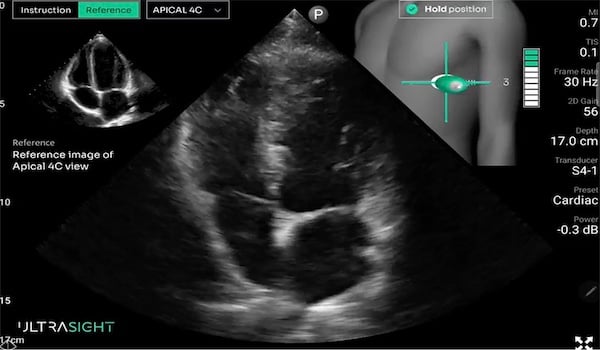

UltraSight’s AI-driven software allows health-care professionals to consistently perform high-quality ultrasound in a variety of settings, including the emergency department and intensive care unit. Photo: UltraSight

Artificial intelligence (AI) brings the promise of expediting cardiac triage by allowing clinicians to perform cardiac ultrasounds at the bedside without sacrificing image quality. One such technology is the Echo Stewardship Platform from UltraSight. It combines real-time AI guidance and a built-in image-quality meter with structured training for non-sonographers.

UltraSight is compatible with most ultrasound devices. The platform processes and stores data inside a health system’s local environment rather than sending it to the cloud, keeping protected health information (PHI) secure. AI within the platform provides users with visual and directional cues. An on-screen meter offers insight into whether images are diagnostic quality.

“What we see as we roll this out across health systems is that it takes about four hours of training and eight scans or less, practicing with physician oversight, for users to get comfortable and confident enough to use our platform,” says Ramya Singh, chief commercial officer at UltraSight.

Dr. West, who has taught novices point-of-care ultrasound for about 10 years, says she wasn’t able to do it without touching the probe until about two to three years ago. “It’s a huge plus to have an AI mentor there to instruct the learner how to move their hand,” she says.